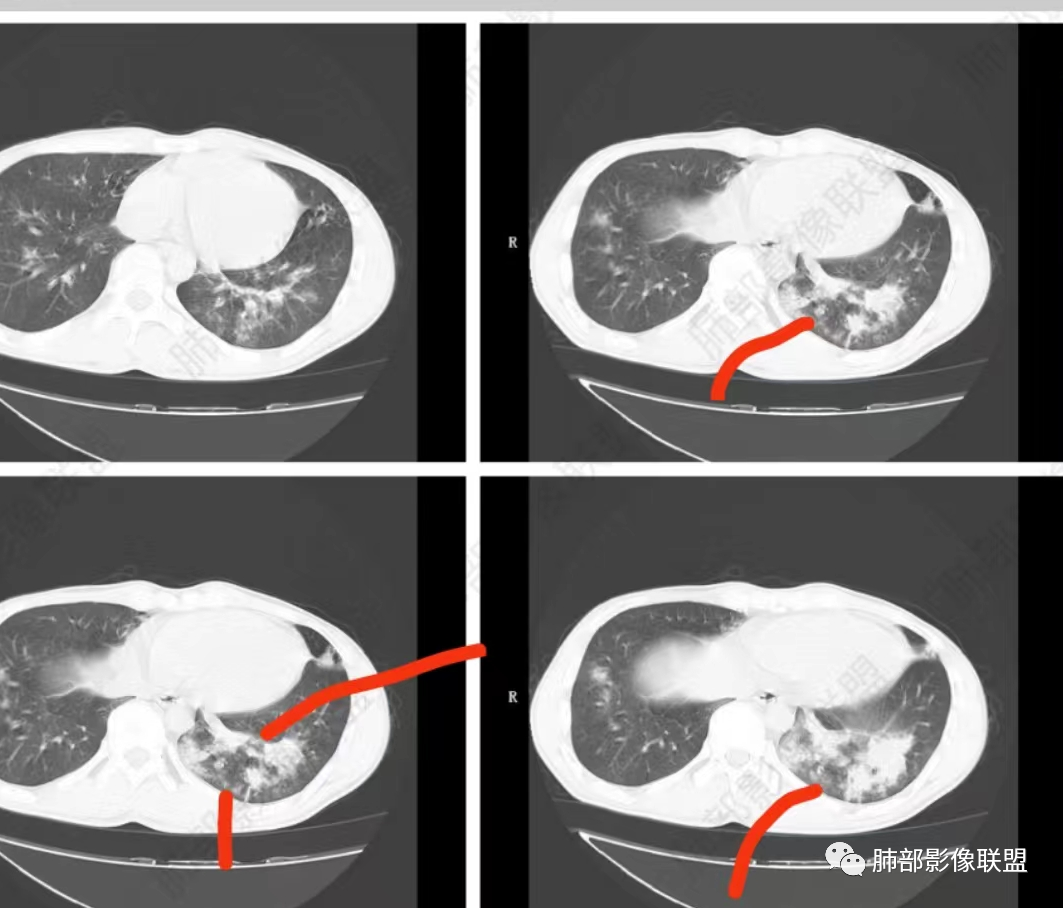

唐老师的经典名言:支扩背景的肺,判断病原体时一定要判断出支扩合并肉芽肿,或无肉芽肿性支扩。

实变边缘太模糊,渗出太明显了,不符合肉芽肿的特点

NTM支扩外一般无渗出性病变,而铜绿支扩外渗出常见

中叶内侧段的渗出病灶内支扩,支持铜绿,不支持NTM

铜绿,与中性粒细胞对话,没有聚集,没有肉芽肿,纤维化不明显。

中叶支扩,周围有渗出,中叶重,也提示专性需氧

你们再看这两个层面!支扩背景下出现肉芽肿病变。